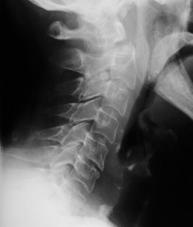

TRAUMA CERVICALA

Incidenta laterala Incidenta

laterala Incidenta

Incidenta oblica Incidenta laterala Incidenta antero-posterioara

Aspect normal Aspect normal Aspect normal